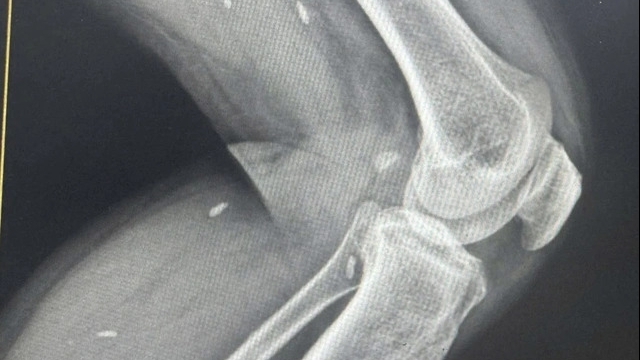

Kết quả siêu âm tại vết thương ghi nhận bên trong vết thương đã lành chứa dịch, còn dị vật, các bác sĩ tiến hành rạch lấy dị vật, mủ, làm sạch, để hở vết thương và phối hợp kháng sinh điều trị nhiễm trùng.